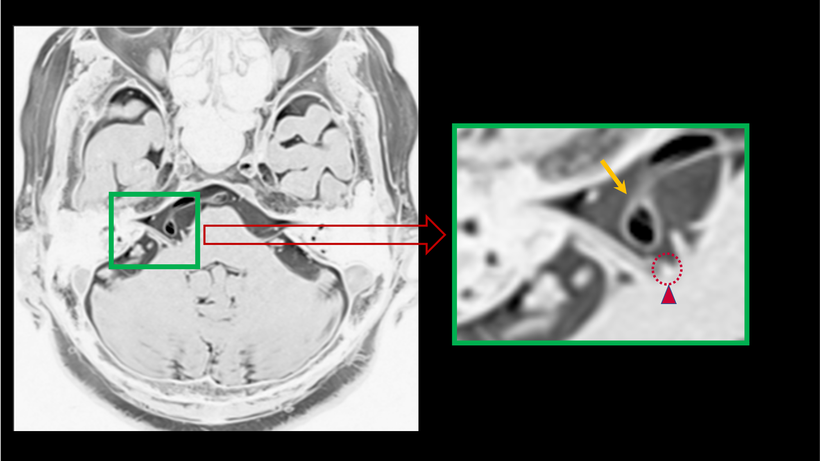

【 顔面痙攣の起きている事がわかるMRI画像-2 】

顔面神経と聴神経との間を走行していた血管(動脈)が、次第に走行を変えていき弓の様な変形をしてしまっている顔面神経(↑)が認められます。これにより、神経根部への血管の走行が認められたり(▲)、顔面神経牽引(点線○)による刺激にて顔面の痙攣が発生します。